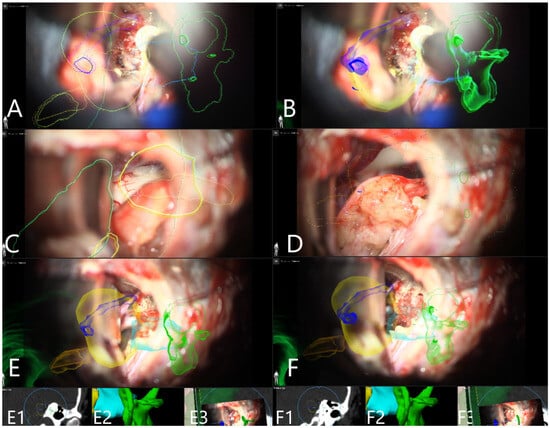

| Patient Number | Segmented Structures in AR Advantages: Craniotomy Planning, Dural Opening, Relations of Tumor to CN V, Localization of Origin of CVI and CVIII at the Brain Stem, Relations of Tumor to Brain Stem, Localization of IV Ventricle, Segmentation of Tumor Cyst, Localization of Structures of the Middle Ear for Facilitation of Drilling on Inner Acoustic Meatus, Relations of Tumor to Arterial Vessels and to Petrosal Vein | ||||||||||

|---|---|---|---|---|---|---|---|---|---|---|---|

| Sigmoid Sinus | Transverse Sinus | Tumor Outline | CN VII and VII Origin at Brain Stem | CN V | Petrous Vein | Arterial Vessels (AICA, PICA, SCA) | Brain Stem | Middle Ear, Cochlea and Semicircular Canals | Pyramidal Tract | IV Ventricle | |

| 28 | + | + | + | − | − | − | + | − | − | − | − |

| 29 | + | + | + | − | − | + | + | − | − | − | − |

| 30 | + | + | + | − | − | + | + | + | − | + | − |

| 31 | + | + | + | − | − | + | − | + | + | − | − |

| 32 | + | + | + | − | − | − | − | + | + | − | + |

| 33 | + | + | + | + | − | − | − | + | − | − | + |

| 34 | + | + | + | + | − | − | − | + | + | − | − |

| 35 | + | + | + | + | − | − | − | + | + | . | − |

| 36 | + | + | + | + | + | − | − | + | − | − | − |

| 37 | + | + | + | − | − | + | − | + | + | − | − |

| 38 | + | + | + | + | + | + | − | + | + | − | − |

| 39 | + | + | + | − | + | − | − | + | + | − | − |

| 40 | + | + | + | + | + | − | − | + | + | − | − |

| 41 | + | + | + | − | + | − | − | + | + | − | − |

| 42 | + | + | + | + | + | − | − | − | − | − | |

| 43 | + | + | + | + | + | + | − | + | + | − | − |